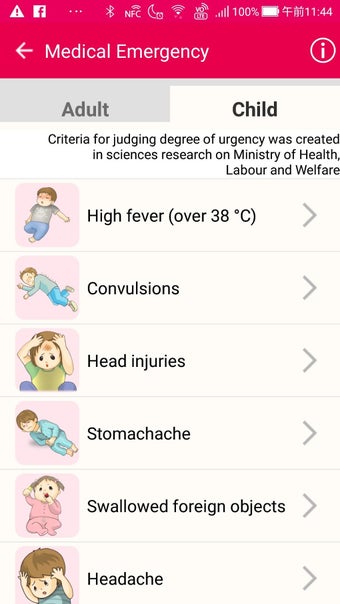

MySOS เป็นแอปพลิเคชันบนมือถือที่ช่วยให้ผู้ใช้เข้าถึงข้อมูลและบริการที่เกี่ยวข้องกับสุขภาพและการดูแลรักษาสุขภาพในประเทศญี่ปุ่น มันถูกออกแบบมาเพื่อให้การช่วยเหลือในกรณีฉุกเฉินทางการแพทย์และรองรับการดูแลสุขภาพและการบริการฉุกเฉิน

เมื่อคุณใช้ MySOS คุณสามารถเข้าถึงข้อมูลและบริการที่เกี่ยวข้องกับสุขภาพและการดูแลรักษาสุขภาพในประเทศญี่ปุ่นได้ คุณสามารถส่งคำขอความช่วยเหลือไปยังผู้ที่คุณไว้วางใจ เช่นครอบครัวหรือเพื่อนของคุณ คุณยังสามารถยืนยันตำแหน่งของ AED หรือโรงพยาบาลที่คุณต้องการไปเยี่ยมชมและส่งคำขอความช่วยเหลือไปยังผู้ที่คุณไว้วางใจได้